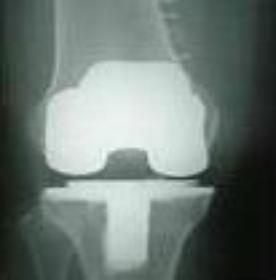

Preparing for Total Joint Replacement